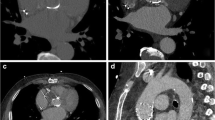

Four currently used mechanical valve aortic prostheses were examined (Fig. 1): St Jude masters bileaflet (SJM, St Jude Medical Inc., St Paul MN), Medtronic Hall tilting disc (MH, Medtronic Inc., Minneapolis MN), Carbomedics aortic reduced bileaflet (CM, Carbomedics Inc., Austin TX), ON-X bileaflet (ON-X Life Technologies Inc., Austin, TX). We chose the same nominal diameter of 27 mm for all valves. Valve leaflets consisted of carbon impregnated with 5 or 10% tungsten and coated with a pyrolytic carbon coating. The valve housing consisted of the prosthetic ring which held the pivot mechanism for the leaflets and a rotation mechanism for the suture cuff. The MH valve had a prominent central titanium strut and a titanium hinge mechanism. Valves were tightly mounted in the PMMA valve chamber ensuring complete fixation during the pump cycle and eliminating potential artifacts generated by movement of the valve as a whole. The MH tilting disc valve was mounted with the largest orifice superiorly. The bileaflet valves were orientated with the leaflets opening vertically.

The four types of mechanical aortic valves used. The St Jude (a) and the Medtronic Hall (b) valve are pictured from below and the Carbomedics (c) and ON-X (d) valve are pictured from above. Note the variable position of the leaflet hinge points. The hinge points are below the level of the housing ring in the St Jude valve (a) and are at the level of the housing ring in the Carbomedics (c) and ON-X (d) valves. The Medtronic Hall valve (b) is the only tilting disc valve and has a housing ring and central struts made of titanium. The elongated housing ring of the ON-X valve contains two titanium rings. (Images courtesy of St Jude Medical Inc., St Paul MN, Medtronic Inc., Minneapolis MN, Carbomedics Inc., Austin TX, ON-X Life Technologies Inc., Austin, TX)

The different thresholds demonstrated various configurations of artifacts (Fig. 2). Specific testing between pairs of static valves indicated differences between all valves for the 2,000, 800 and 200 HU thresholds (Table 1, p < 0.001). For the −50 HU threshold no difference was found between the ON-X and CM valves (p = 0.43) but all other differences were significant (p < 0.001). The differentiation of the volume attributable to radiopaque components of the valve such as the ring and the leaflets from the total 200 HU threshold volume is demonstrated in Fig. 3. Specific testing between specific components demonstrated significant differences between ring volumes: 480 ± 3, 745 ± 12, 611 ± 12 and 147 ± 3 mm3 for the SJM, MH, CM and ON-X valve respectively (all differences p < 0.001). The leaflet volumes were 975 ± 11, 1,111 ± 25, 1,101 ± 15, and 1,336 ± 8 mm3 for the SJM, MH, CM and ON-X valve respectively. No difference existed between the CM and MH valve (p = 0.33), but the SJM and the ON-X had respectively a smaller and a larger leaflet volume than the other valves (p < 0.001). The artifact volumes (without leaflet and ring components) were 3,546 ± 141 mm3 for the SJM, 2,387 ± 103 mm3 for the MH, 2,003 ± 102 mm3 for the CM, and 3,033 ± 31 mm3 for the ON-X valve (all differences p < 0.001).

A Sagittal view of a St Jude valve prosthesis on multiplanar reformatting (a). The valve is placed in the mounting ring of the valve chamber which is inserted in the thoracic phantom at a 45° angle to the CT gantry. Volume rendered images of the same valve with the −50 (b) and 200 (c) threshold. The 800 threshold (d) includes prosthetic ring and leaflets and the 2,000 threshold (e) includes only the prosthetic ring